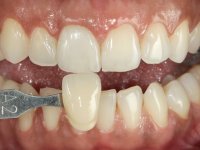

A pre-print was performed to make a crown in dual-cured resin. After a cross-section with a turbine, the infiltrated crown was removed with a microluxador. The dental stump was re-prepared to better define the shape and location of the cervical margin. It was necessary to place composite resin on the buccal surface of the provisional crown to improve its esthetics. The impression was made using a double-mix technique with two-viscosity, quick-setting silicones. In the laboratory, a crown with a ceramic-coated Zr infrastructure was made. After placing it in the mouth, we verified that the crown showed a greater translucency than the symmetrical one, not fulfilling our aesthetic goals. The ceramist had the opportunity to observe the situation in the clinic, collecting records for later rectification. The new crown was placed in the mouth and approved by the patient. The final cementation was done with resin-reinforced glass ionomer cement.